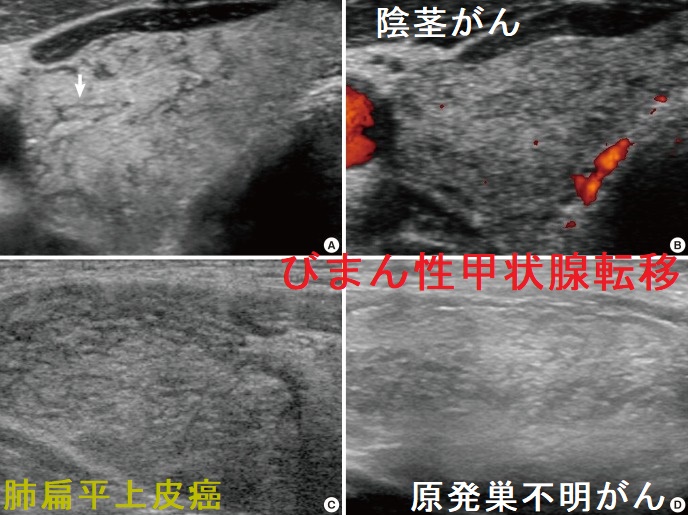

びまん性甲状腺転移をおこす癌として、

- 肺癌

- 原発巣不明がん

- 胆管がん

- 陰茎がん

- 乳癌 [World J Clin Cases. 2022 Jan 21;10(3):1106-1115.]

- 胃印環細胞癌[J Med Ultrason (2001). 2017 Jan;44(1):133-139.]

などがあります。甲状腺びまん性硬化型乳頭癌(DSPTC)との鑑別要。

超音波(エコー)検査では、甲状腺全体がびまん性に腫大し、内部は低エコーまたは等エコーで不均一。低エコー線(樹枝状低rコー)を伴い網状パターン(癌性リンパ管炎)。[J Korean Med Sci. 2014 Jun;29(6):818-24.]

甲状腺組織の破壊により甲状腺機能低下症をきたす。